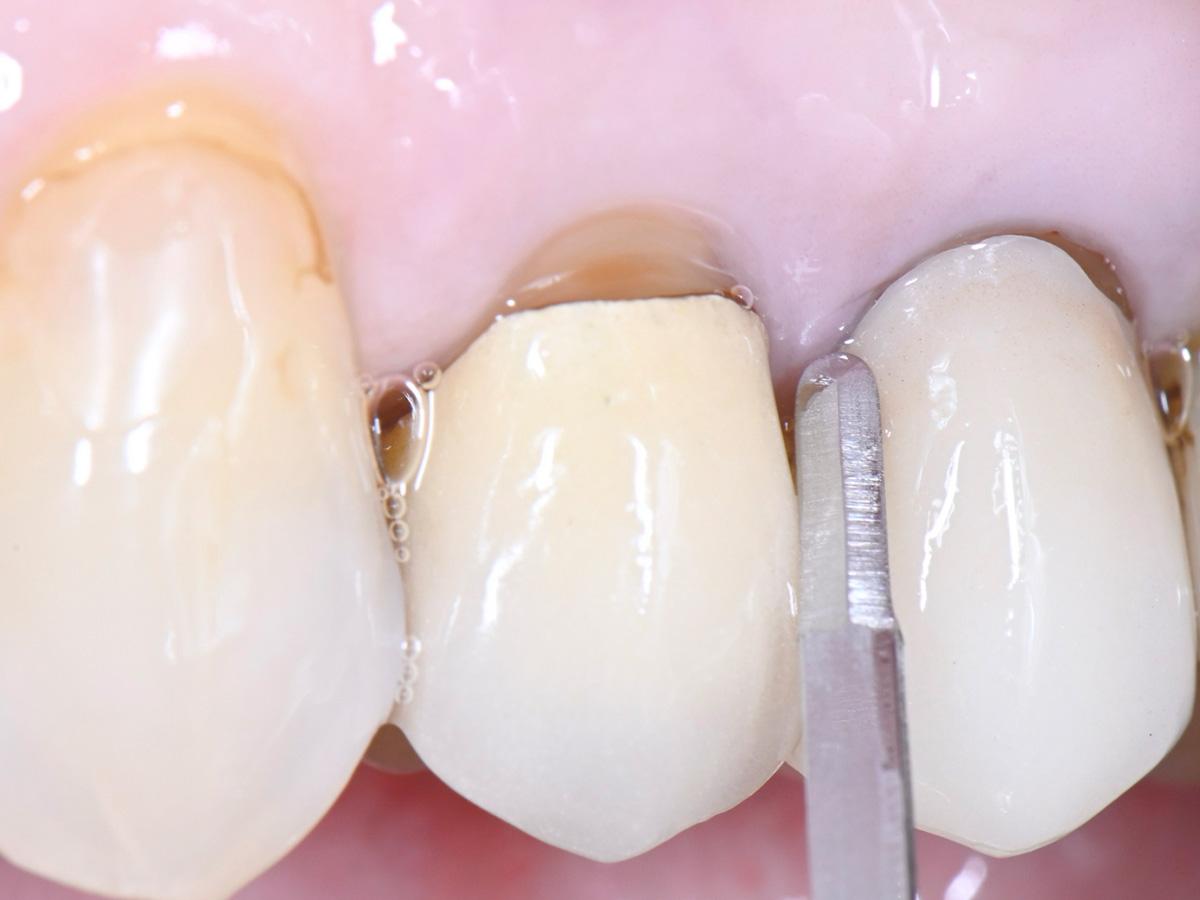

Abbildung 3

Intrasulkuläre Inzision um den nicht erhaltungswürdigen Zahn mit der Micro Blade SR